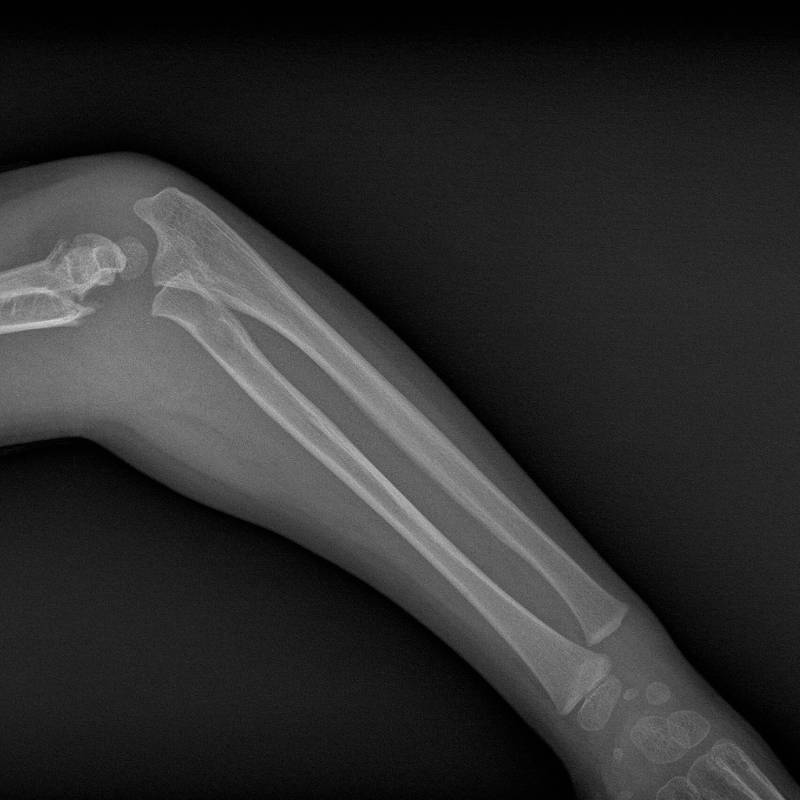

Digunakan untuk menilai tulang lengan bagi kecederaan atau kelainan.

Pemeriksaan sinar-X pada tulang lengan bawah.